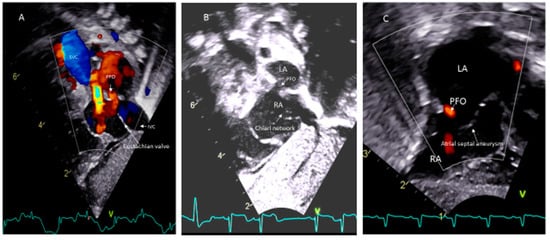

- Hubail, Z.; Lemler, M.; Ramciotti, C.; Moore, J.; Ikemba, C. Diagnosing a patent foramen ovale in children. Is transesophageal echocardiography necessary? Stroke 2011, 42, 98–101. [Google Scholar] [CrossRef] [PubMed]

- Silvestry, F.E. Guidelines for the echocardiographic assessment of atrial septal defect and patent foramen ovale from the American Society of Echocardiography for cardiac angiography and interventions. J. Am. Soc. Echocardiogr. 2015, 28, 910–985. [Google Scholar] [CrossRef]